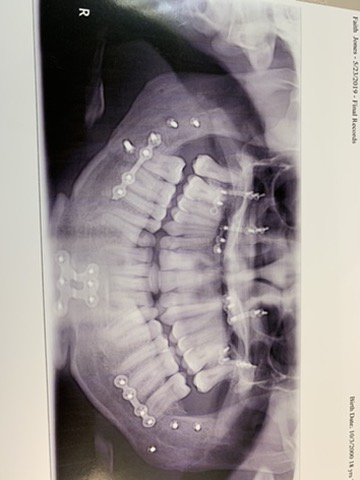

Fourwheeler accident. Xray 6 months after surgery, steel plates and screws on top and bottom

This is used after jaw bone surgery. Its calle Maxillomandibular fixation. Mandible is lower jaw and maxilla is the upper jaw bone.

The primary reason is for a fractured jaw.